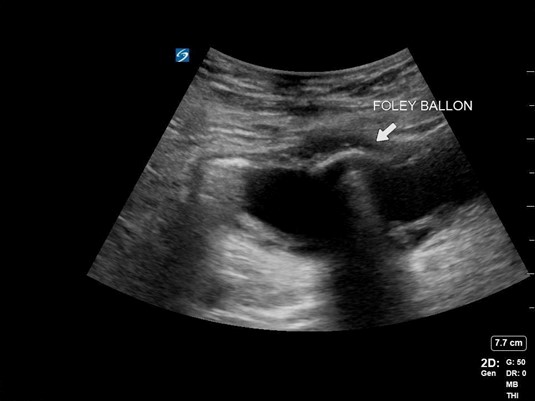

A 59-year-old male with a longstanding history of BPH and urinary retention presented with a chief complaint of suprapubic abdominal pain and non-draining of his foley catheter. He stated that his catheter was changed every 8 weeks and had just been changed the prior month. On examination, his catheter was found to be obstructed with urinary sediment and clot and was removed with a plan for exchange. When the new catheter was placed and the balloon inflated, the patient reported significant pain. A POCUS image of the bladder revealed the following:

Figure 4. Image of foley balloon inside bladder

Foley catheter insertion can be challenging in the patient with BPH. POCUS can be especially useful in identifying the location of the catheter, with the balloon creating a hypoechoic shadow artifact. When the patient’s urinalysis resulted, he was found to have a catheter-associated UTI (CAUTI) causing his pain, but the catheter was appropriately placed.